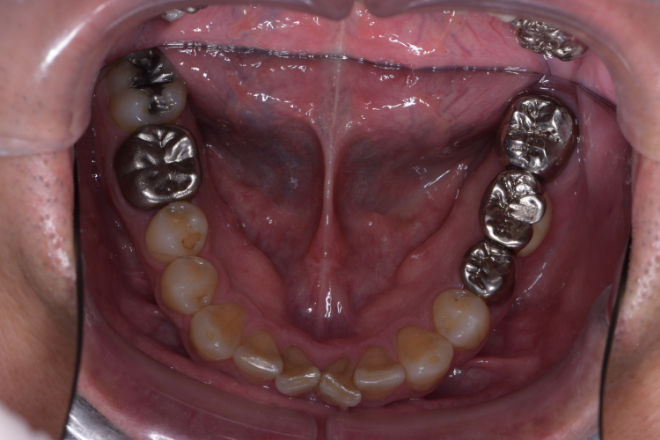

| 備考 | 右上の欠損部へのインプラントを希望で来院されました。 左下のブリッジの下にものが挟まりやすいとのことでブリッジ部分もインプラント埋入を希望されました。口腔内の銀歯も全て綺麗にやりかえたいとのことで、ダイレクトボンディングやセラミックインレーやジルコニアクラウンでやりかえていきました。 右上6番のインプラント埋入時にはソケットリフトで骨造成を行なっています。 見た目だけではなく噛みやすくなりとても満足されています。現在はエアフローのクリーニングやホワイトニングで通院されています。 |